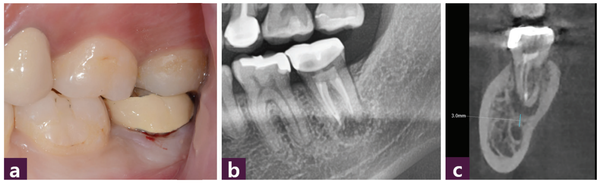

식립 직후부터 1개월, 3개월, 4개월마다 각각 연조직 치유과정, 파노라마, CBCT 촬영에 따른 ISQ 수치 변화를 관찰했다. [그림 6, 7, 8]

중등도 이상의 치주 질환에서 발치 후 즉시 식립의 골 치유 과정은 발치와 치유 과정과 같은 secondary bone healing 과정을 겪는다. 이러한 치유과정을 파노라마와 CBCT로는 관찰하기 힘들기 때문에 ISQ 수치를 활용해 골 치유과정을 관찰했으며 식립 4개월 후에 기대하고 있던 ISQ 수치 60에 근접했음을 확인하고 최종 보철을 장착했다. [그림 9. 10]